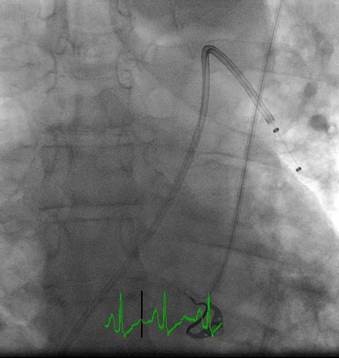

Angiografía de la arteria pulmonar izquierda realizada con un catéter en espiral de 6 F en ángulo, que demuestra la presencia de un trombo de gran tamaño dentro de la arteria pulmonar izquierda y en las bifurcaciones lobulares intermedia e inferior.

Se efectuó una trombectomía reolítica con el catéter PE de AngioJet® mediante un catéter guía multifunción de 8 F a través de una guía de angioplastia hidrófila de 0,035’’.

Angiografía pulmonar izquierda realizada tras una trombectomía reolítica en la que se muestra la mejora del índice de perfusión y obstrucción.